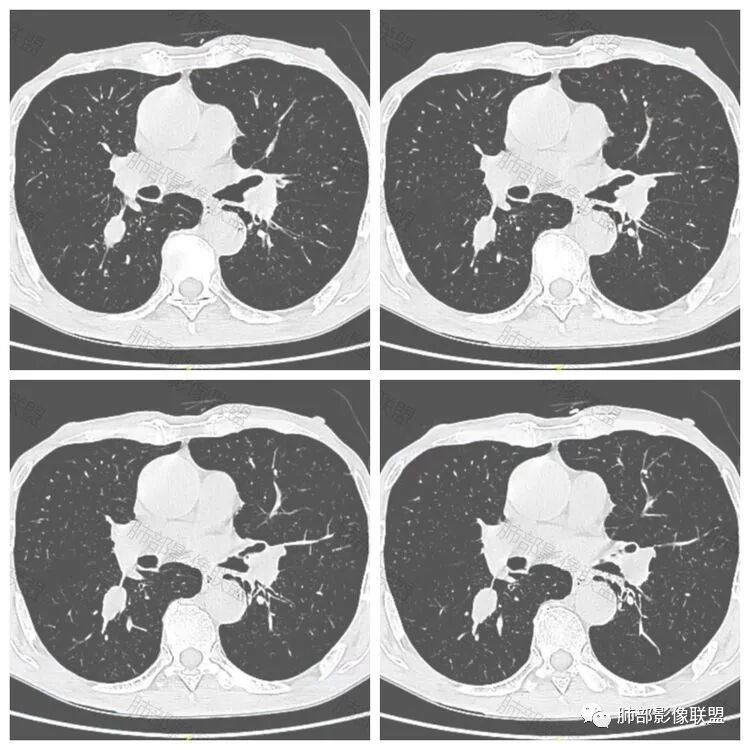

老年男性患者,胸部隐痛1月入院,有长期吸烟史,胸部CT:右肺下叶背段梭型结节灶,边界清晰,无明显分叶、毛刺及周边磨玻璃影,内部密度不均匀,支气管截断,增强扫描不均匀轻度强化,内部似乎见支气管黏液栓,纵隔淋巴结不大,考虑恶性病变:小细胞癌(缺少典型的纵隔肺门淋巴结增大融合),鳞癌(病史复合,但没有阻塞性肺炎,内部没有坏死,),类癌(多见于女性患者,与吸烟关系不大),首先考虑典型类癌,

老年男性,右肺下叶梭形或椭圆形结节,形态较规则,边缘光整,支气管截断,增强不均匀轻度强化,右肺门及纵隔淋巴结增大,考虑恶性病变,鳞癌或小细胞癌,神经内分泌癌(小细胞形)。

老年男性患者,右肺下叶背段梭形结节影,边界比较光整,密度均匀,没有明显的分叶毛刺,没有阻塞性肺炎的表现,这些感觉具备有良性的特点。而近端支气管截断,增强明显的强化,纵隔多发的淋巴结,显得是恶性的特点。总体印象,老年患者+支气管截断征象+明显强化的结节+纵隔多发淋巴结,还是考虑恶性结节,小细胞癌或是鳞癌。

男性,老年人,长期吸烟史,老慢支背景,右下肺背段占位,支气管亚段门口堵,病灶长轴与支气管平行,推测腔内生长可能,病灶内血管穿行,周围干净,轻度强化,右肺门淋巴结肿大,考虑恶性,神经内分泌癌(大小类)>淋巴上皮瘤样癌>腺癌>鳞癌

右肺下叶梭形实性结节,密度均匀,边缘光整,局部膨隆,近端支气管截断,轻度强化,血管走行自然,右肺门及纵隔淋巴结增大,考虑小细胞癌>鳞癌

右肺下叶背段结节,沿着支气管走行呈长椭圆形,边缘圆滑清晰,近端支气管阻塞,远端支气管有沿壁增厚,右肺门淋巴结肿大,中度强化,老年男性,吸烟病史,肺气肿背景,考虑小细胞肺癌,鉴别鳞癌

老年男性,吸烟史,右肺下叶梭形肿块,边缘平直有分叶,支气管近端阻塞,右肺门肿大淋巴结,增强后轻度强化,欠均匀,首先考虑恶性,小细胞肺癌?

老年男性,吸烟史,右肺下叶背段梭型软组织肿块,边缘膨隆,不均匀强化,近端支气管截断,同侧肺门及纵隔淋巴结肿大,支持恶性,小细胞可能大,鳞癌缺少阻塞性改变

晨读,右下叶梭形占位,边界光滑,支气管截断,可见尾征,不均匀轻度强化,肺门淋巴结肿大,有吸烟史,高龄高危患者,首先考虑恶性,考虑小细胞癌,鉴别一下鳞癌

老年男性,前胸隐痛1月。2年前有白内障手术史。右下肺结节,沿中轴呈梭形,膨隆,边清、无分叶,无毛刺,近端支气管截断完全堵塞,病灶以远未见阻塞性炎症及肺不张。内部密度基本均匀,增强轻微强化,似见局部低密度影。纵隔及右肺门见肿大淋巴结。整体考虑恶性可能性大,小细胞癌?鳞癌?注意鉴别良性结节—错构瘤。

老年男性,长期吸烟史,右肺下叶背段梭形低密度灶,边界清晰,无明显分叶、毛刺,边缘稍彭隆,支气管截断,右肺门淋巴结增大,增强扫描不均匀轻度强化(延迟略明显),首先考虑恶性,小?不典型结核球待排。

右肺下叶背段结节,气管堵塞,密度均匀,边界清晰,无明显分叶、毛刺,边缘膨隆,右肺门淋巴结增大,增强轻度强化,考虑小细胞癌,鉴别鳞癌。

右肺下叶梭形软组织结节,密度均匀,明显尾巴,边缘光整,近端支气管截断,轻度强化,血管走行自然,又腊肠尾巴征象

男,83,前胸部隐痛不适1月。有长年大量吸烟史。胸部CT:肺气肿,右肺下叶纺锤型实性结节灶,边界清晰,支气管截断,内部密度不均匀,增强扫描不均匀强化,右肺门淋巴结大。考虑恶性病变:小?鳞?鉴别炎性肉芽肿、错构瘤等。

晨读:老年男性+吸烟+右肺下叶与气管长轴一致的梭形肿块影+支气管截断,轻度强化,右肺门肿大淋巴结,考虑恶性,小细胞肺癌可能,鉴别鳞癌

呈典型管状改变,近端支气管堵塞、稍扩张,病灶有强化倾向于恶性,没有强化倾向于炎性病变(结核之类);近端呈结节状(鳞癌多一些),这个病例呈管状(小细胞Ca多一些);平扫与强化有差异,有轻度强化,是粘液栓还是血管?